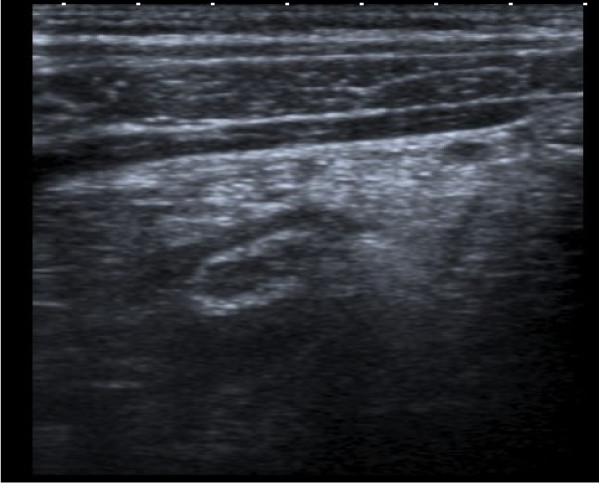

We report the case of a 43 year old male with acute onset of abdominal pain who had undergone an appendicectomy ten years previously. Ultrasound revealed the presence of an inflamed tubular structure. Subsequent laparotomy and histology confirmed that this structure was an inflamed residual appendiceal tip.

我们报告一例43岁男性病例,该患者急性腹痛起病,10年前曾接受阑尾切除术。超声检查显示存在一个发炎的管状结构。随后的剖腹手术及组织学检查证实该结构为发炎的残余阑尾尖端。